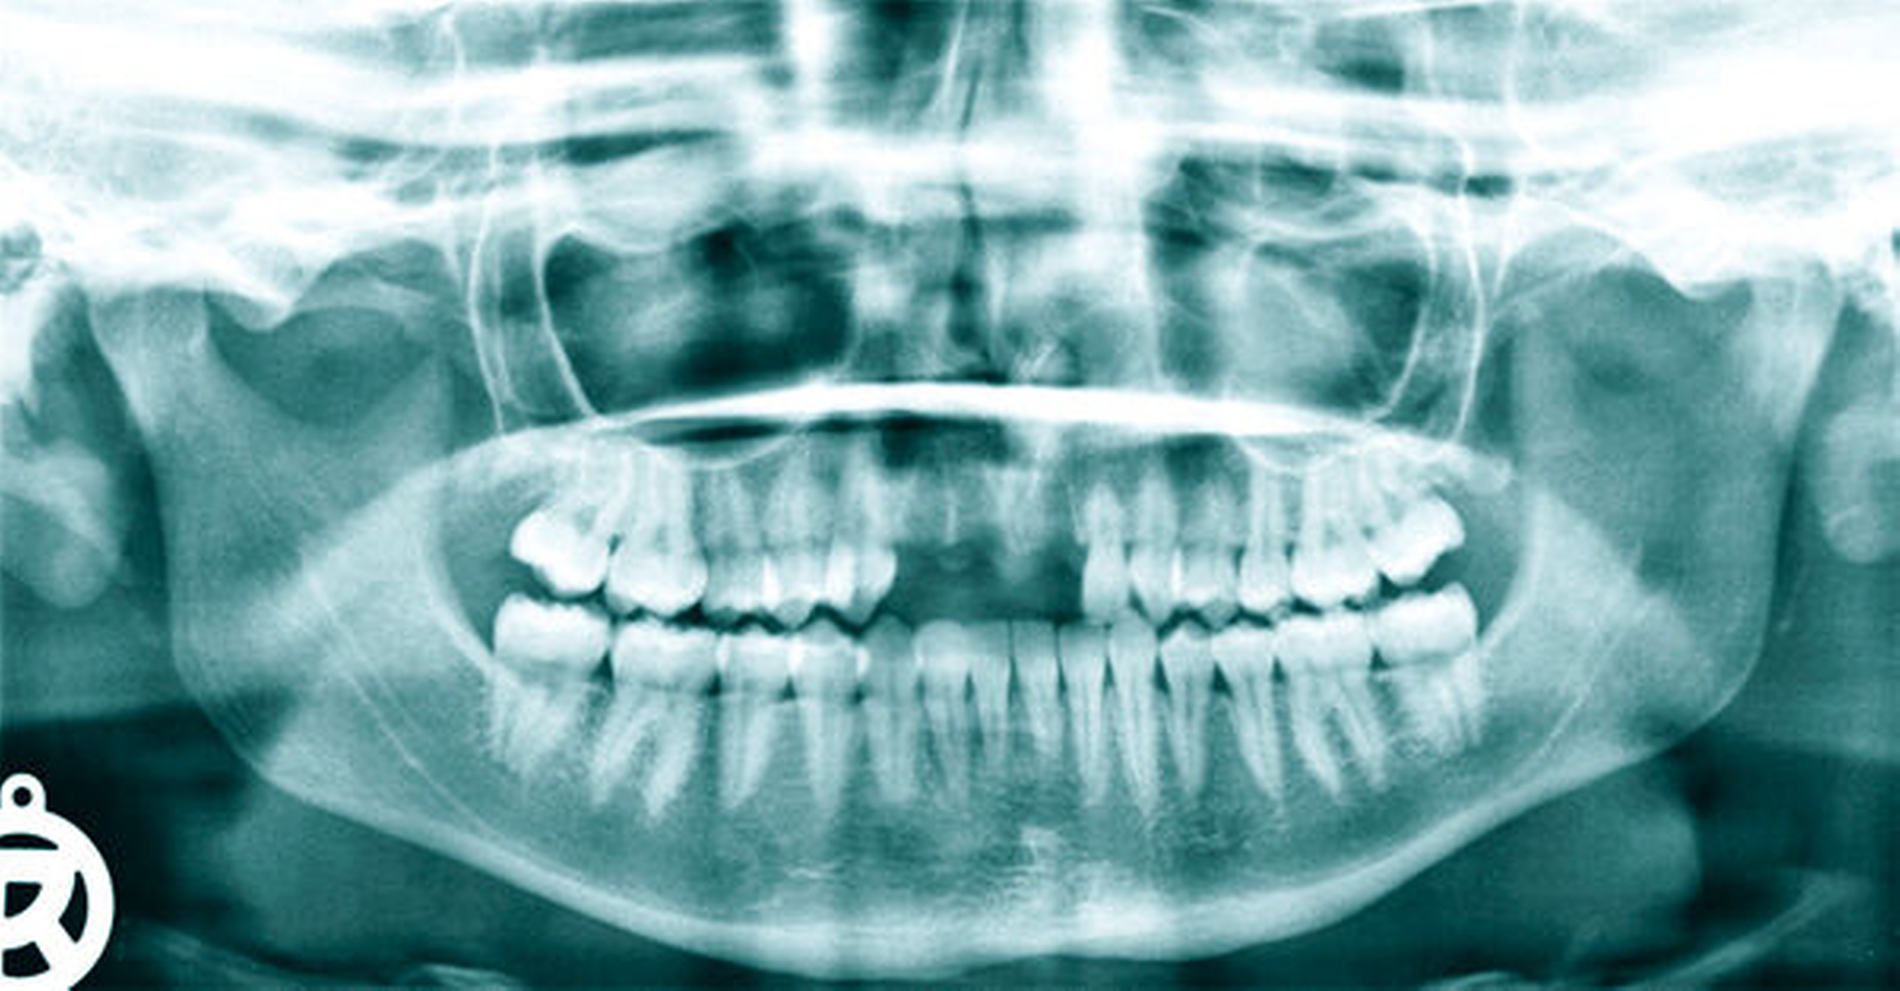

Aufgrund des Unfallmechanismus wurde ergänzend eine Computertomografie der Kopf-Hals-Region veranlasst (Abbildung 2), die lediglich minimale ossäre Begleitschäden der involvierten Zahnfächer nachwies. Weitere ossäre Traumafolgen und eine akute intrakranielle Blutung konnten somit ausgeschlossen werden. Das OPTG (Abbildung 3) zeigte die leeren Zahnfächer 12, 11, 21. Die übrigen Zähne wurden durch den Sturz nicht beschädigt. Mit Zustimmung der Patientin wurde gemeinsam mit der diensthabenden Gastroenterologin ein endoskopischer Bergungsversuch der Zähne geplant, um diese möglichst zu replantieren.